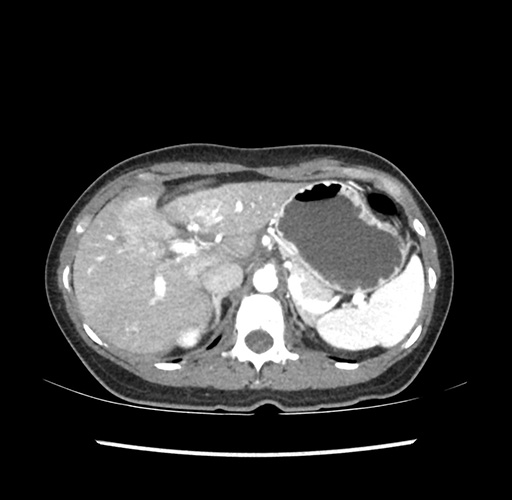

Imaging Analysis

Look through the patient's CT scan to identify any areas of concern for the necessary procedure.

Based on your CT findings, which issue(s) would give reason for "planned slowing down moment(s)" in this case?

Considering a standard left lateral sectionectomy procedure, what step(s) of the operation would you do differently in this case ?